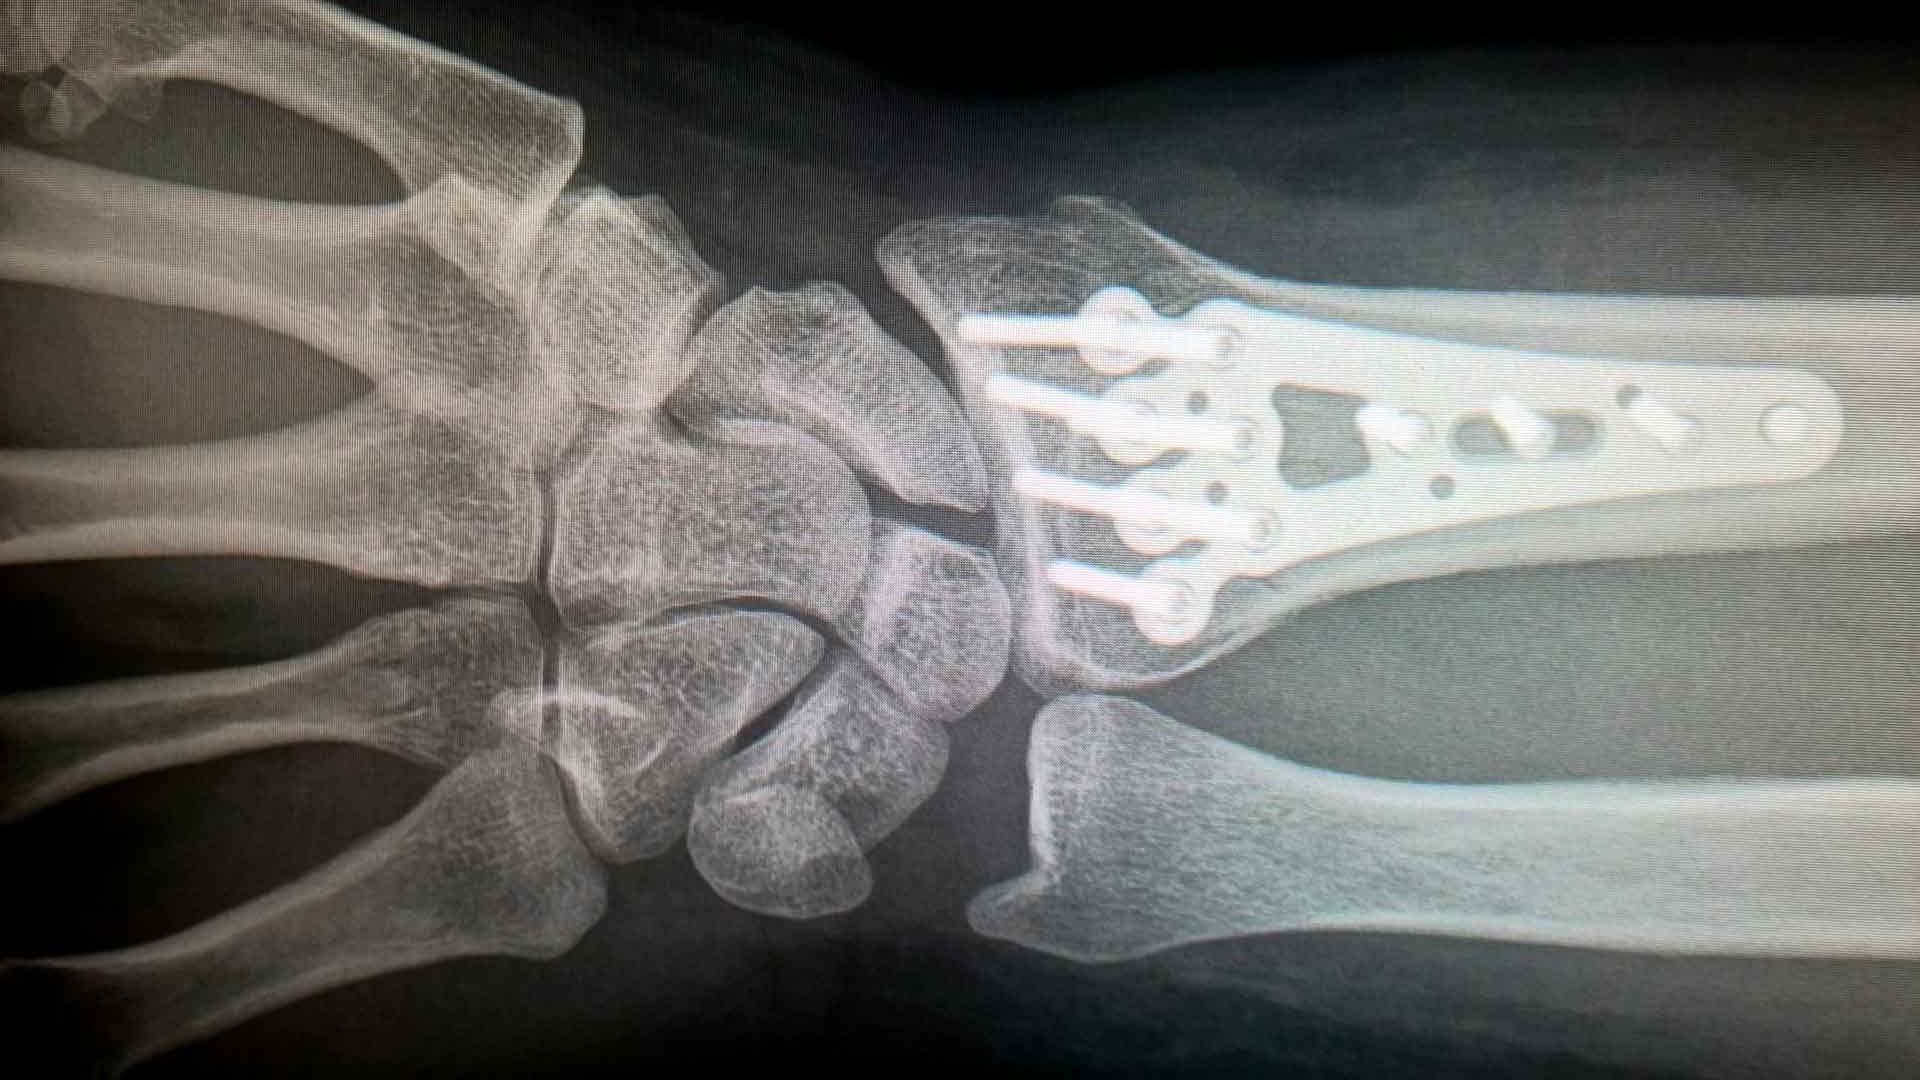

Es una disciplina fundamental para la recuperación de pacientes que han sufrido lesiones musculoesqueléticas o traumas en el sistema locomotor. Esta rama de la fisioterapia se enfoca en evaluar, diagnosticar y tratar afecciones como secuelas de fracturas, esguinces, luxaciones, lesiones de tejidos blandos y otras lesiones relacionadas con traumatismos.

La fisioterapia en traumatología es esencial para ayudar a las personas a recuperarse de lesiones y traumas musculoesqueléticos, restaurar su movilidad y reducir el dolor. Los fisioterapeutas especializados en esta área desempeñan un papel crucial en el proceso de recuperación y en la prevención de futuras lesiones.